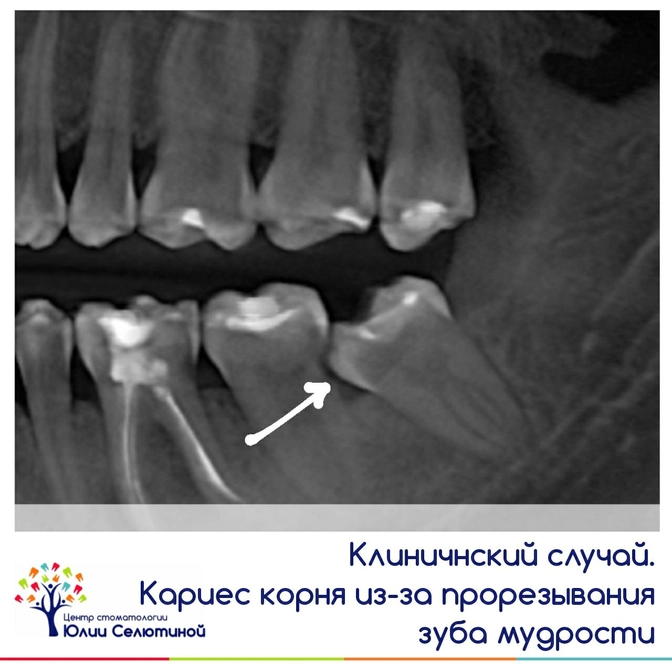

Клинический случай: кариес корня из-за прорезывания зуба мудрости.

Всё внимание на снимок:

- зуб мудрости рос под углом и упирался в соседний седьмой зуб;

- на месте контакта он спровоцировал разрушение — задета не только коронковая часть, но и корень.

Повреждение зуба вскрылось, когда сделали снимок.

Диагноз сразу ясен: зуб мудрости ("восьмерку") нужно удалять, а соседний седьмой зуб ("семерку") лечить, иначе есть риск и ее потерять.